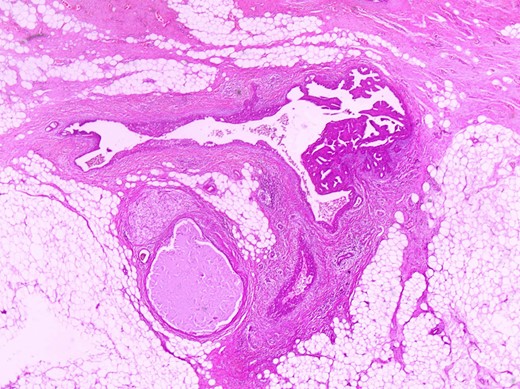

The histologic examination revealed an intraductal papilloma of 9 mm in maximum diameter with no evidence of atypia or malignancy (Figs 3,4 and 5).

Partially dilated duct with papillary projections within its lumen (in the right side of it) (H+Ex400).